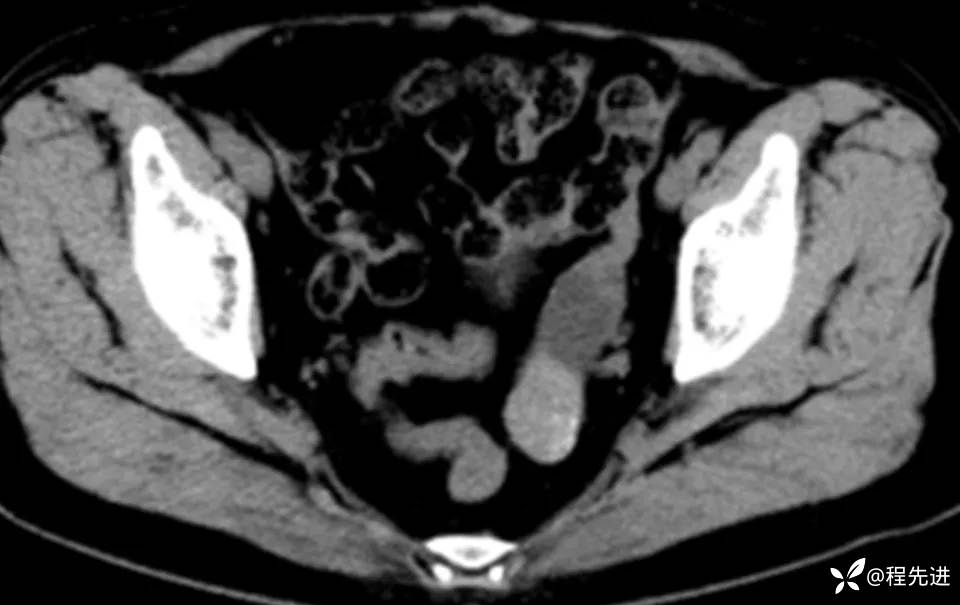

患者性别:女

患者年龄:60岁

简要病史:诊断乙状结肠癌术前常规检查发现

CT平扫+增强: